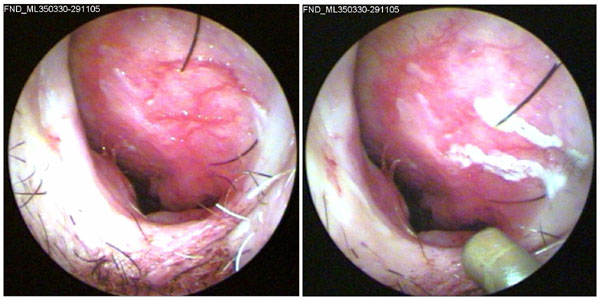

JFC Cauterización de epistaxis con nitrato de plata.